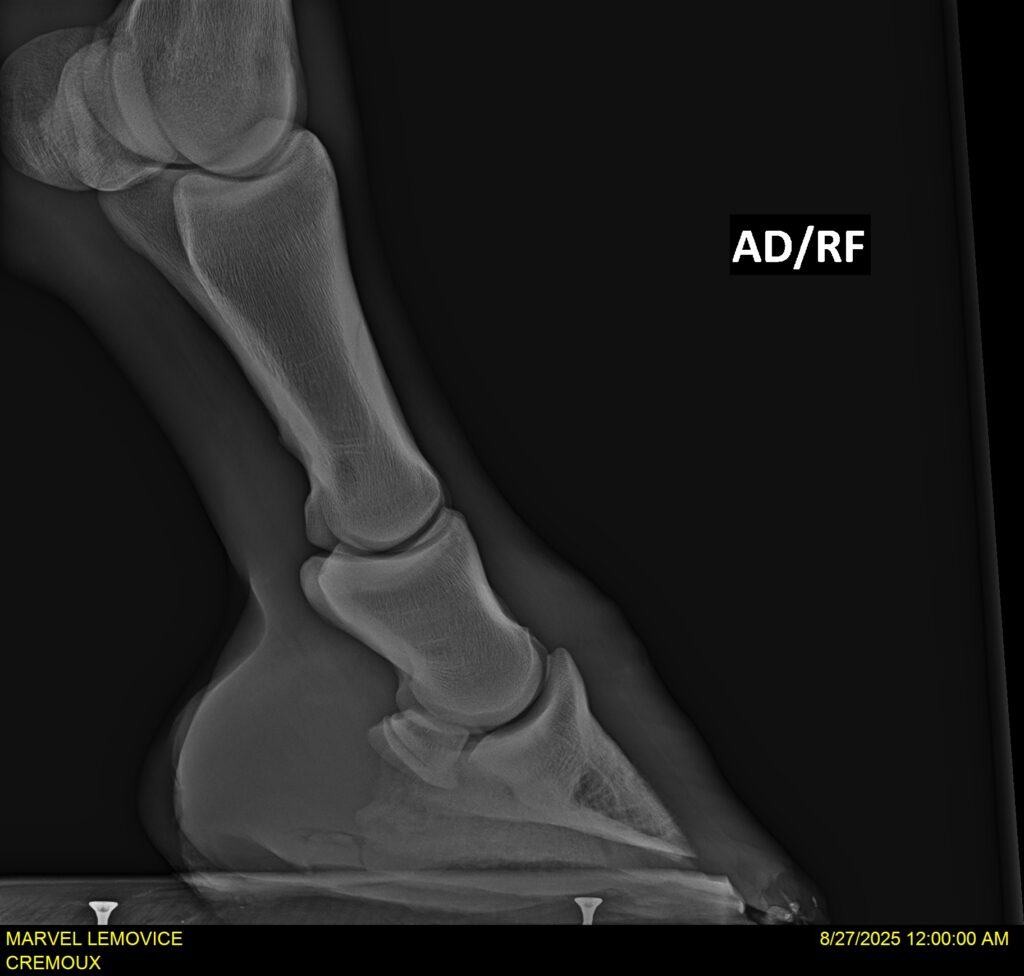

MARVEL LEMOVICE, hongre, Selle Français prend 4 ans en 2026. POPSTAR LOZONAIS x ROSIRE sur une excellente souche maternelle de l’élevage PLATIERE. Débourré aux trois allures et mise en route à l’obstacle. Super modèle avec du cadre et de la force, cheval respectueux avec des moyens. Très agréable au quotidien. Transport OK, maréchalerie OK, santé RAS, Bilan 20 clichés radios + clinique OK.

RADIOS ET CLINIQUE